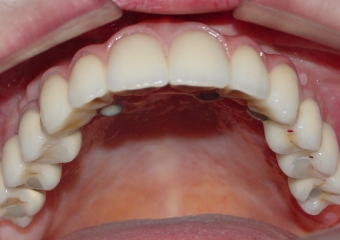

Imagens finais do caso terminado em agosto de 2010

Sorriso final